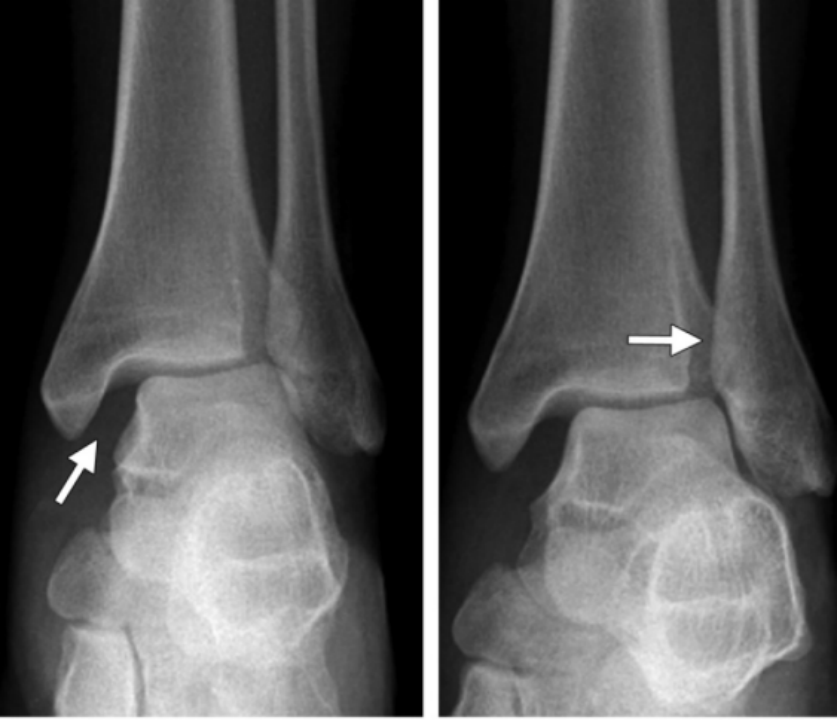

1、旋后(内翻)内收损伤(简称 SA)

损伤时,足呈旋后位,距骨内收,使踝关节外侧韧带紧张。

旋后内收损伤

Ⅰ度:首先发生的是外侧副韧带撕裂或者外踝的撕脱骨折,由于损伤发生于下胫腓联合远端,该韧带多保持完整。

I 度损伤 X 线显示:外踝间隙增宽,提示外侧副韧带撕裂,未见胫腓骨骨折,此型在 X 线上是隐匿的。

Ⅱ 度:内收的外力继续作用,内踝受内翻的距骨挤压作用,可造成内踝的垂直骨折,及胫骨远端关节面的内侧部分压缩骨折,如果合并其他方向的外力,有可能造成内踝的斜行骨折。

II 度损伤 X 线片显示:腓骨骨折在下胫腓联合水平以下,内踝垂直骨折;侧位 x 线片显示后踝无骨折。